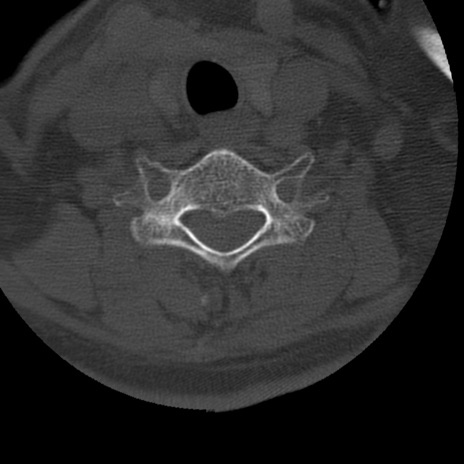

症例50 頚椎CT(横断像)

頚椎CT